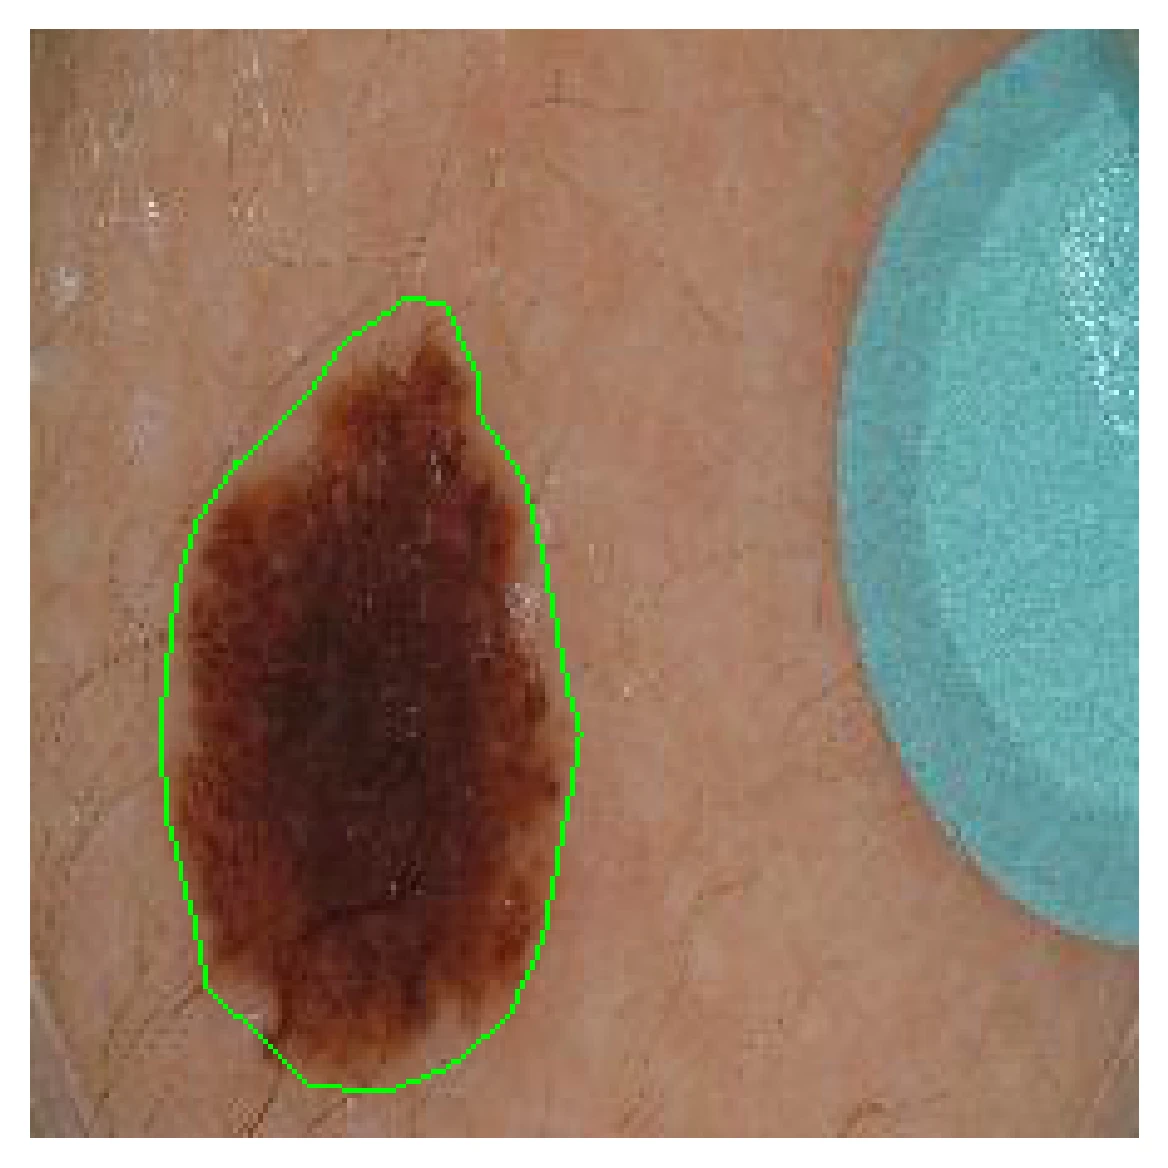

Segmentation Style Discovery: Application to Skin Lesion Images

Medical Image Computing and Computer-Assisted Intervention (MICCAI) ISIC Skin Image Analysis Workshop (MICCAI ISIC), 2024

StyleSeg learns plausible, diverse, and semantically consistent segmentation styles without annotator correspondence, outperforming competing methods while maintaining alignment with annotator preferences. [Abstract] [BibTeX] [Presentation Slides]

Variability in medical image segmentation, arising from annotator preferences, expertise, and their choice of tools, has been well documented. While the majority of multi-annotator segmentation approaches focus on modeling annotator-specific preferences, they require annotator-segmentation correspondence. In this work, we introduce the problem of segmentation style discovery, and propose StyleSeg, a segmentation method that learns plausible, diverse, and semantically consistent segmentation styles from a corpus of image-mask pairs without any knowledge of annotator correspondence. StyleSeg consistently outperforms competing methods on four publicly available skin lesion segmentation (SLS) datasets. We also curate ISIC-MultiAnnot, the largest multi-annotator SLS dataset with annotator correspondence, and our results show a strong alignment, using our newly proposed measure AS2, between the predicted styles and annotator preferences. The code and the dataset are available on GitHub.